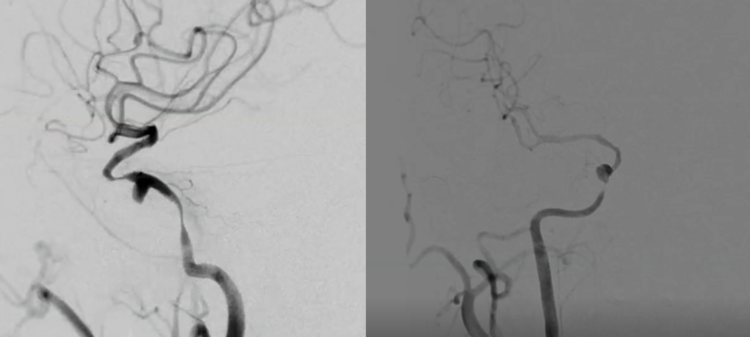

右侧颈内动脉正侧位DSA造影提示海绵窦段较小动脉瘤,瘤体远近端均存在严重狭窄。

颈内动脉海绵窦动脉瘤的诊断明确,虽然造影显示DSA动脉瘤很小,通过症状病史结合影像,考虑动脉瘤为大型病变,近期可能急性血栓形成,导致动脉瘤体增大,对海绵窦结构和视神经产生压迫,引起出现头痛和视力下降等症状,但是诱发急性血栓形成的因素无法确认,瘤体远近端的狭窄是动脉硬化性还是血栓生长的结果,从影像上无法确认。